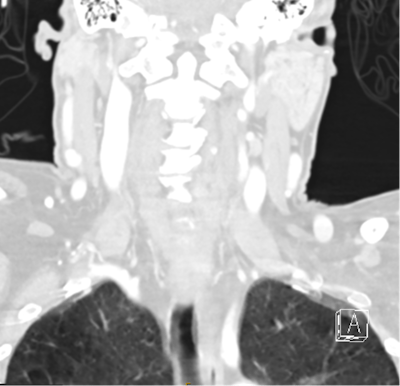

Another example of an incidental finding not being communicated to the patient's GP. CT cervical spine coronal reconstruction for a patient in their 50s who presented to the emergency department after syncope with head injury. The radiologist documented incidental emphysematous changes within the lung fields that were captured on a brain and cervical spine CT. This patient was a current smoker who had had no previous investigation, diagnoses, or treatment for chronic obstructive pulmonary disease (COPD).